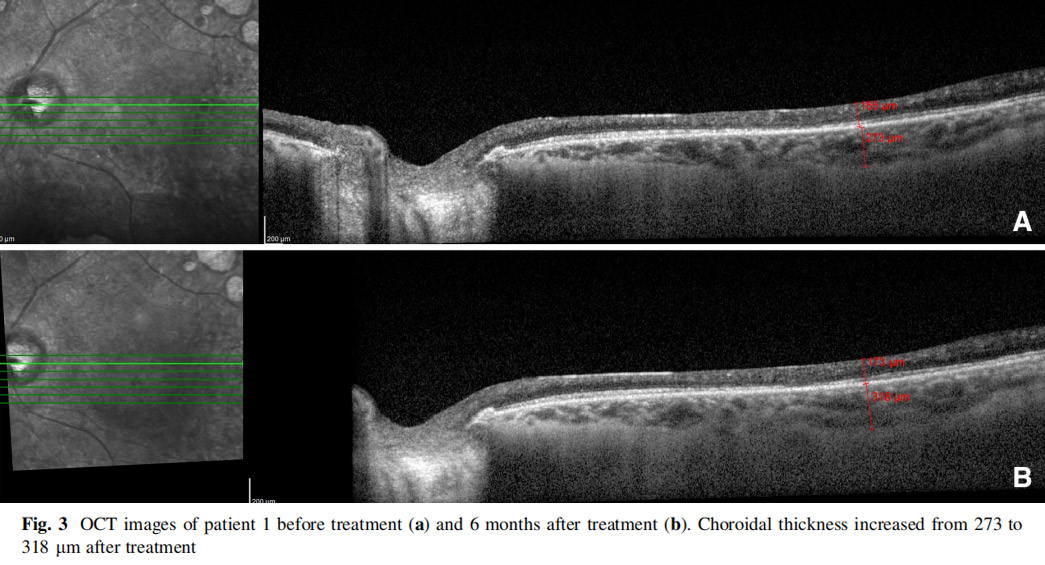

患者左眼接受AD-MSCs治療,6個(gè)月后視力提高至2米處數(shù)手指(CF)水平,視野中央島狀結(jié)構(gòu)擴(kuò)大,如圖1所示,左眼mfERG顯示改善(圖2),脈絡(luò)膜厚度從273μm增加至318μm(圖3),黃斑厚度和RNFL沒(méi)有變化。